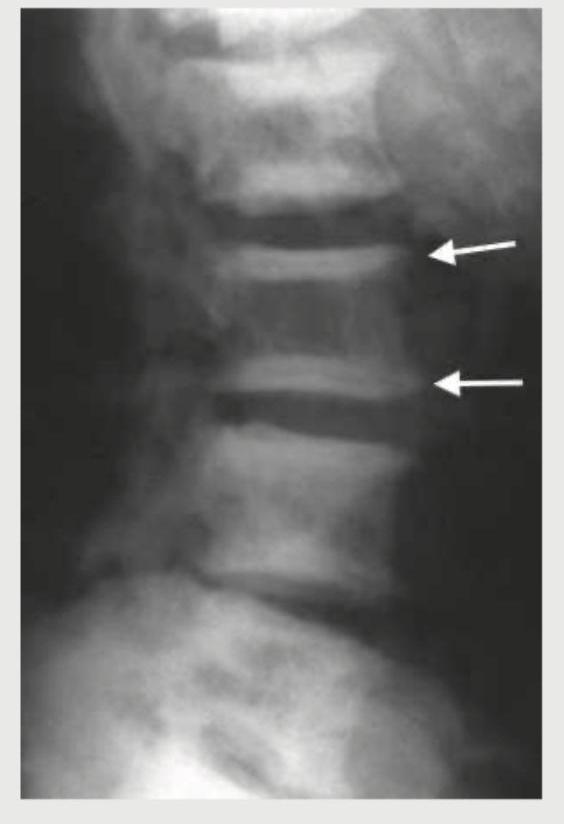

A 28-year-old female with chronic kidney disease presents with bone pain and elevated parathyroid hormone levels. She has a history of renal stones. What is the sign visible in the image?

Explanation: ***Rugger-jersey spine*** - The image exhibits alternating bands of dense and lucent bone in the vertebral bodies, which is characteristic of the **rugger-jersey spine** sign. - This sign is classically seen in **renal osteodystrophy due to secondary hyperparathyroidism**, which occurs in chronic kidney disease. - In secondary hyperparathyroidism, the dense bands represent increased osteosclerosis at the vertebral endplates, while the central lucent areas reflect increased bone resorption. *Trummerfeld zones* - These are zones of **reduced mineralization** in the metaphyses of long bones, typically seen in **rickets** or **scurvy**. - They are not associated with the vertebral changes seen in the image or the clinical scenario of chronic kidney disease with secondary hyperparathyroidism. *Vertebra plana* - Refers to a vertebra that has **collapsed** to a flat, disc-like shape, often maintaining its cortical margins. - It is typically caused by conditions like **eosinophilic granuloma**, metastatic disease, or severe osteoporosis, none of which fit the radiographic appearance of rugger-jersey spine. *Looser zones* - These are also known as **pseudofractures** and are radiolucent lines that represent uncalcified osteoid, characteristic of **osteomalacia**. - They are typically seen in specific locations like the femoral neck, pubic rami, and scapula, not in the vertebral bodies as shown in the image.